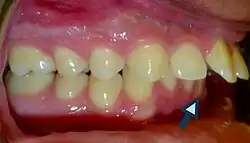

• Dental carious lesions are a predisposing cause of tooth fractures (Lubisich et al., 2010) due to the already weakened and undermined dental hard tissues.

• Patients with increased overjet or lip incompetence are also at a higher risk of suffering traumatic injuries in the upper incisors (Schatz et al., 2020).

Overjet